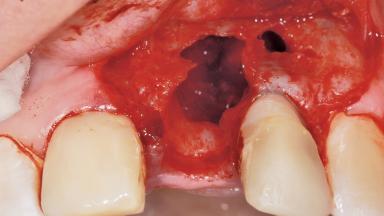

Late Placement of an Implant in a Maxillary Left Central Incisor Site

A 36-year-old female patient was referred for the replacement of the upper left central incisor (tooth 21), which had fractured. Although the tooth had been asymptomatic for many years, the crown began to loosen, at which time she presented to her dentist for an assessment. Teeth 21 and 22 had both been endodontically treated many years previously. She was a healthy individual and a non-smoker.

Bone Augmentation Horizontal|Staged

Augmentation Materials Xenogenous|Membrane

Bone Volume Deficient horizontally, requiring prior grafting